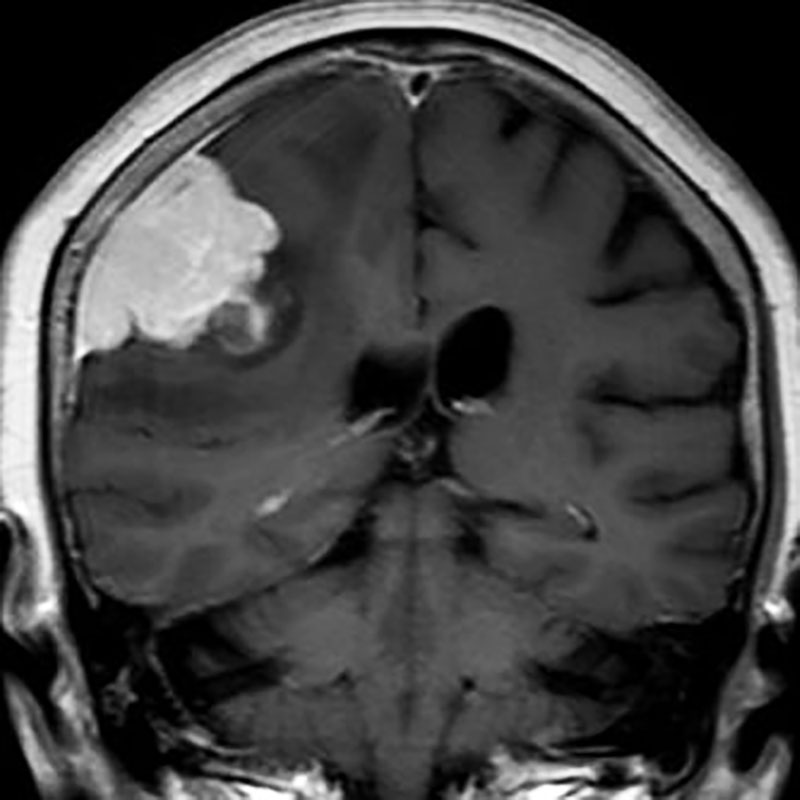

285

'22年4月

70代

膠芽腫

頭蓋内腫瘍摘出術

No.’22_42 手術前1

No.’22_42 手術前2